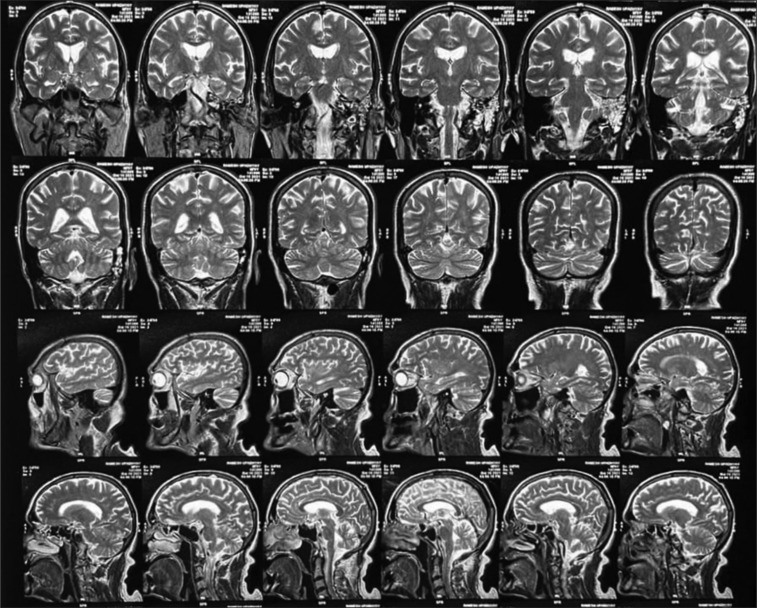

紧张症是一种以行动不便和交流障碍为特征的复杂综合征,在不同认知障碍和潜在痴呆的个体中,对劳拉西泮治疗的反应不同。本研究检查了一个病例系列,涉及四个不同的紧张性精神病患者,以阐明影响劳拉西泮反应的因素。虽然劳拉西泮作为一种gaba能调节剂,在某些情况下可以有效缓解症状,但其在其他情况下的有限影响突出了各种痴呆的潜在病理生理和治疗机制之间复杂的相互作用。本摘要提供了对神经化学通路、紧张症症状和治疗方法之间复杂关系的见解,揭示了在认知障碍和痴呆的背景下管理紧张症的复杂性。

Catatonia, a complex syndrome characterized by immobility and communication impairment, presents with varying responses to lorazepam treatment among individuals with different cognitive impairments and underlying dementias. This study examines a case series involving four distinct catatonic patients to elucidate the factors contributing to the variable lorazepam response. Although lorazepam, a GABAergic modulator, can effectively alleviate symptoms in some cases, its limited impact in others highlights the intricate interplay between the underlying pathophysiology of diverse dementias and treatment mechanisms. This abstract provides insights into the intricate relationship between neurochemical pathways, catatonic symptoms, and treatment approaches, shedding light on the complexities of managing catatonia in the context of cognitive impairments and dementias.